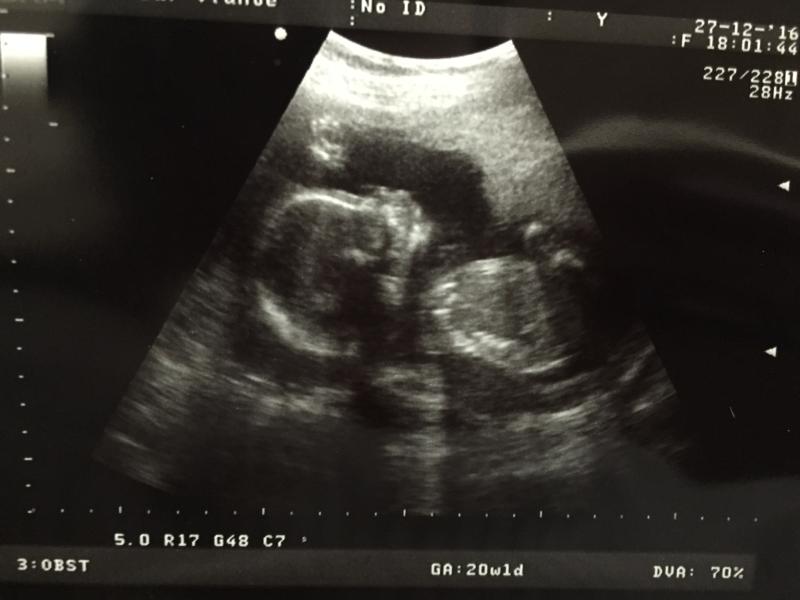

Сегодня сделали второй скрининг. Срок от последних месячных-20 недель и 1 день, но на УЗИ показывает значение как 19 недель и 3 дня 🙄 Паника тихо меня настигает😬 предыдущая беременность этим и закончилась:в 25 недель мне поставили диагноз-отставание в развитии на 5 недель и много пороков, которые не видели в 20 недель. В 26 недель прерывание беременности.

Неужели история повторяется?😭 или рано ещё паниковать?

У вас срок в срок были показания на УЗИ????? 🙏🏻